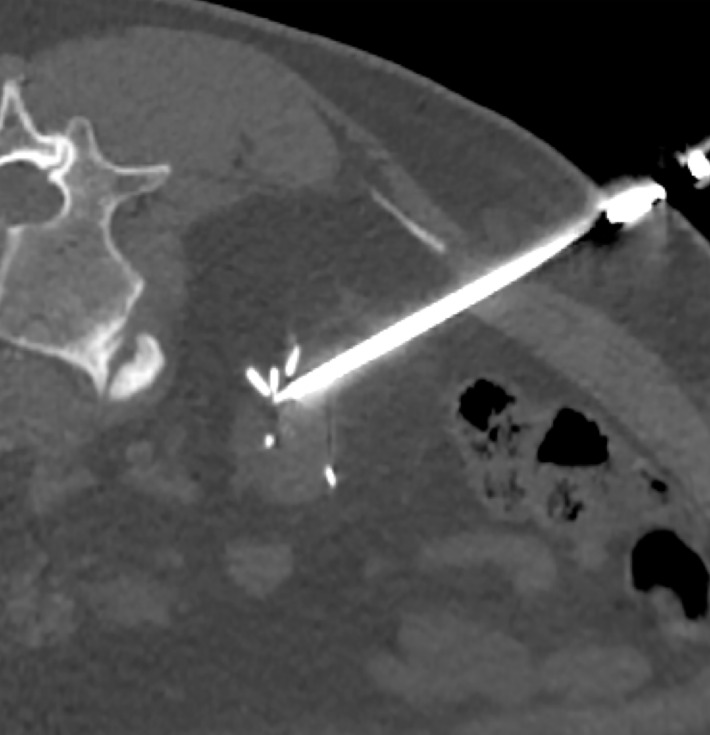

Aim: This study presents our experience with using percutaneous cryoablation (PCA) to manage recurrences and new masses in previously operated kidneys.

Materials and methods: We conducted a retrospective data analysis to evaluate patients treated with PCA for tumor recurrence or residual disease in the postresection bed, excluding those with de novo or recurrent tumors in the contralateral kidney.

Results: A total of 23 individuals met the inclusion criteria. Of those, 14 initially underwent laparoscopic PN, and 9 were treated with open surgery. The median interval from the initial surgery to recurrence‑targeted PCA was 23 months (range, 7-228). The mean (SD) RENAL score on admission was 7.5 (1.9), and the median (interquartile range) tumor volume was 3 (1.6-4.5) ml. The median length of hospital stay was 23 hours (range, 6-55). There was no significant change in estimated glomerular filtration rate following cryoablation. All the recorded complications, except one, were grade I and resolved with hydration or treatment with nonsteroidal anti‑inflammatory drugs. No patient required dialysis in the perioperative period.

Conclusions: Imaging‑guided PCA is a feasible and effective treatment option for patients with renal tumor recurrences after PN.